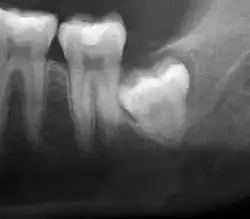

Impacted wisdom teeth are classified by their direction of impaction, their depth compared to the biting surface of adjacent teeth and the amount of the tooth's crown that extends through gum tissue or bone. Impacted wisdom teeth can also be classified by the presence or absence of symptoms and disease. Screening for the presence of wisdom teeth often begins in late adolescence when a partially developed tooth may become impacted. Screening commonly includes a clinical examination as well as x-rays such as panoramic radiographs.

If the tooth cannot be assessed with clinical exam alone, the diagnosis is made using either a panoramic radiograph or cone-beam CT. Where unerupted wisdom teeth still have eruption potential several predictors are used to determine the chance of the teeth becoming impacted. The ratio of space between the tooth crown length and the amount of space available, the angle of the teeth compared to the other teeth are the two most commonly used predictors, with the space ratio being the most accurate. Despite the capacity for movement into early adulthood, the likelihood that the tooth will become impacted can be predicted when the ratio of space available to the length of the crown of the tooth is under 1.[6]: 141